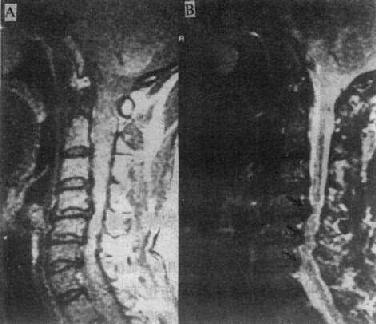

MRI可清楚地显示椎管狭窄,包括椎体与脊椎小关节的增生、韧带肥厚和椎间盘脱出等。如果椎间盘脱出发生在多个平面,且相对的黄韧带肥厚,则在与椎间隙水平相对应的硬膜囊前后缘受压,在矢状面T2WI上,硬膜囊呈串珠状表现(图2-2-4)。

图2-2-4p; 颈椎关节病颈4~6段的蛛网膜下腔及脊髓于椎间盘水平均受压变细,呈典型的糖葫芦状